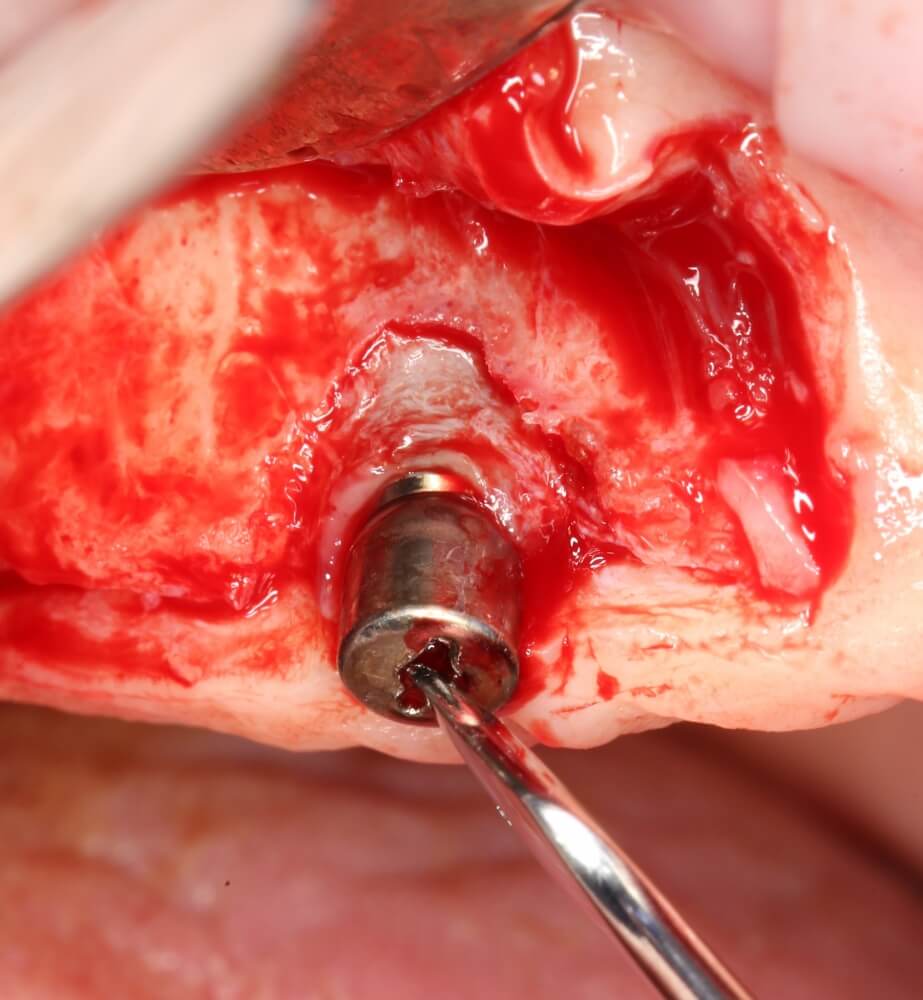

Прежде, чем приступить к аугментации (пластике) лунок зубов, мы подготовили лунки для имплантатов. В таких клинических случаях нет необходимости в использовании шаблона. Вместо этого, мы применяем общепринятые правила позиционирования и соблюдаем рекомендации производителя по хирургическому протоколу:

В процессе ирригации лунки промываются, что позволило нам еще раз подтвердить ранее сделанные выводы. С помощью аналогов имплантатов, входящих в хирургический набор Xive, мы проверили возможность стабилизации имплантатов в будущих лунках. Исходя из правил подбора и позиционирования имплантатов (я очень рекомендую почитать об этом здесь>>) мы остановились на Xive S диаметром 3,4 мм и длиной 13 мм.